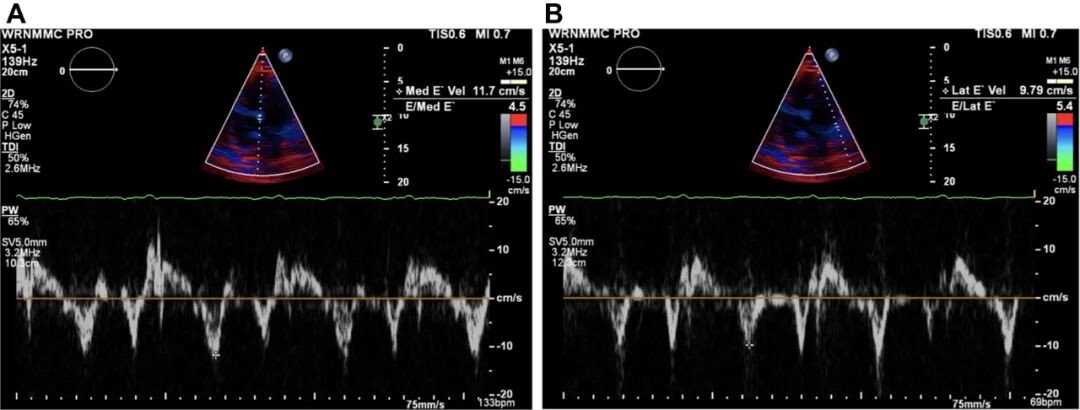

组织多普勒成像显示二尖瓣环内侧和外侧的早期舒张速度(e')分别为11.7cm/s和 9.79cm/s(图 1)。

图1. 组织多普勒成像显示,二尖瓣环内侧壁的早期舒张速度(e′)速度为11.7cm/s(A),而外侧壁的速度(e′)较低,为9.79cm/s(B)。

组织多普勒成像有助于鉴别CP和限制性心肌病,后者也可出现奇脉、库斯莫尔征、显著的y降支和平方根征。在CP中,二尖瓣环外侧壁的峰值早期舒张速度(e')低于内侧e'速度,导致瓣环逆转(图 1)。这被认为是由于外侧二尖瓣环被邻近的纤维化心包束缚所致,通常在限制性心肌病中不常见。

3.瓣环逆转是组织多普勒成像的一个发现,即二尖瓣环外侧e'速度低于内侧e'速度,有助于鉴别CP和限制性心肌病。